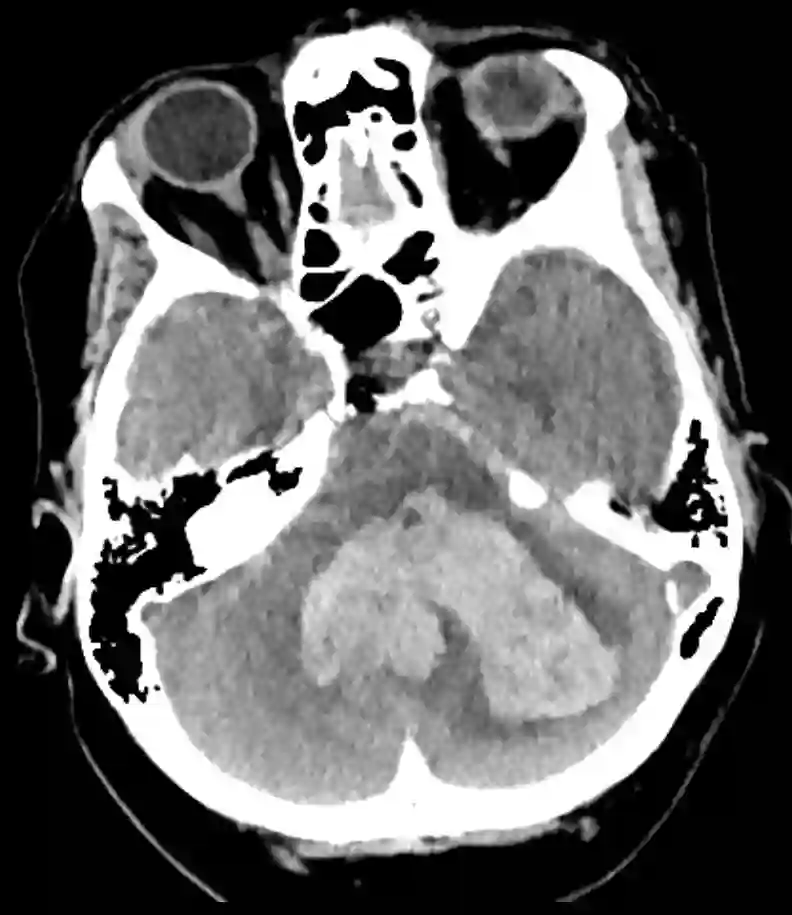

Cerebelläre Blutung im CT

Ausgeprägte cerebelläre Einblutung im axialen CT Bild.